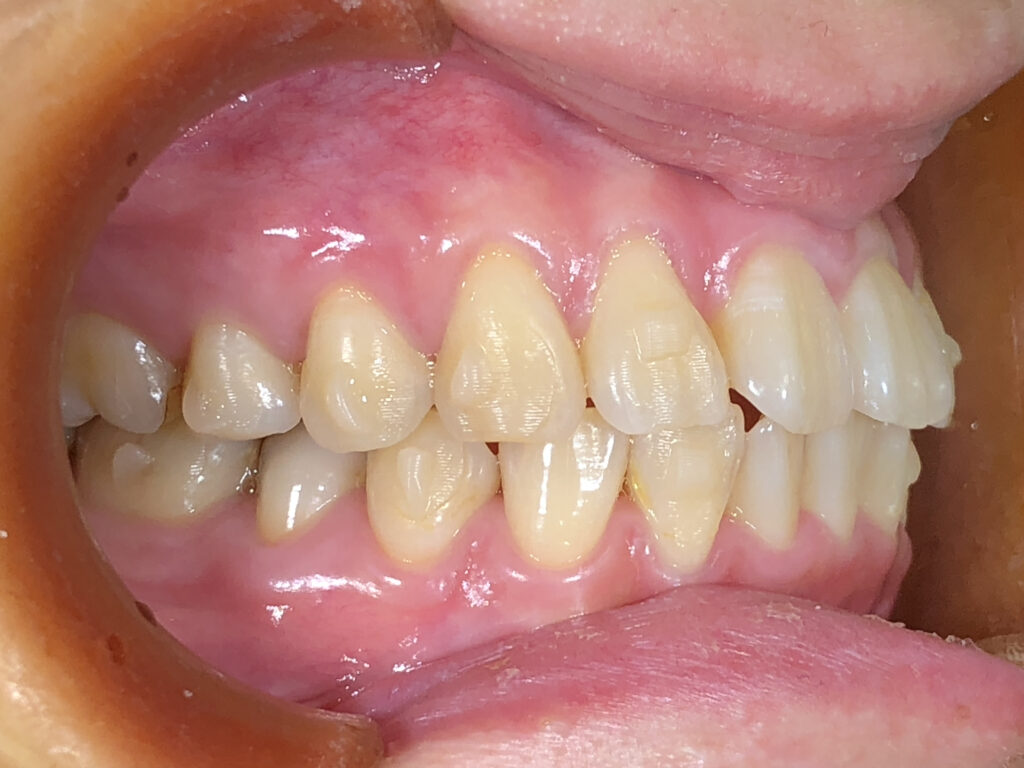

左側

治療前

治療後